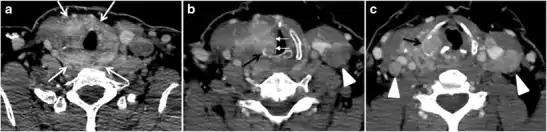

Thyroid calcifications on a CT scan can be seen in both benign and malignant thyroid lesions. Sonographic examination of the thyroid can differentiate between micro-calcifications, which are highly associated with papillary thyroid carcinoma, and eggshell calcifications, which favour a benign process such as colloid cysts (Figs. 1 and 2). In a retrospective review of preoperative CT scan, 35% (135 of 383) of the patients had detectable intrathyroidal calcifications. Among them, 48% had a histopathologically proven thyroid cancer. Calcified nodules had a significantly higher incidence of thyroid cancer and lymph node metastases. The incidence of thyroid cancer among nodules with different calcifications patterns was 79% of nodules with multiple punctate calcifications, 58% of nodules with a single punctate calcification, 21% of nodules with coarse calcification, and 22% of nodules with peripheral calcification. Most of the single calcified nodules were malignant. However, this did not include patients with ITNs and the sample is skewed towards malignancy. Another study evaluated the presence of ITNs on CT scans and found that 12% of thyroid nodules were calcified, with no significant correlation between malignant or potentially malignant histology and punctate calcifications. As a result, some researchers believe that calcification per se is not a suspicious CT sign, and have suggested that calcified thyroid nodules on CT scans should be treated the same as non-calcified nodules.[1]

Fig. 1. An incidentally discovered colloid nodule with calcification, shown on CT scan of a 58-year-old female patient. a Non-enhanced axial CT scan of the neck demonstrates a coarse calcification at the left thyroid inferior pole. b Sagittal grey scale ultrasound of the thyroid demonstrates a heterogeneous nodule with a predominant cystic component. Calcification was not seen in the ultrasound, probably due to its lower location in the superior mediastinum.[1]

Fig. 2. A 51-year-old female patient post left hemithyroidectomy, with incidentally discovered a right thyroid colloid nodule on CT scan. an Enhanced axial CT scan of the neck demonstrates a well-defined, hypodense right thyroid nodule (white arrow) with no internal calcifications or cervical lymphadenopathy. b Transverse greyscale thyroid ultrasound demonstrates a well-defined, hypoechoic right thyroid lobe nodule with a central echogenicity including comet tail (ring down) artefacts (white arrow). No vascularity (not shown) or calcifications were detected.